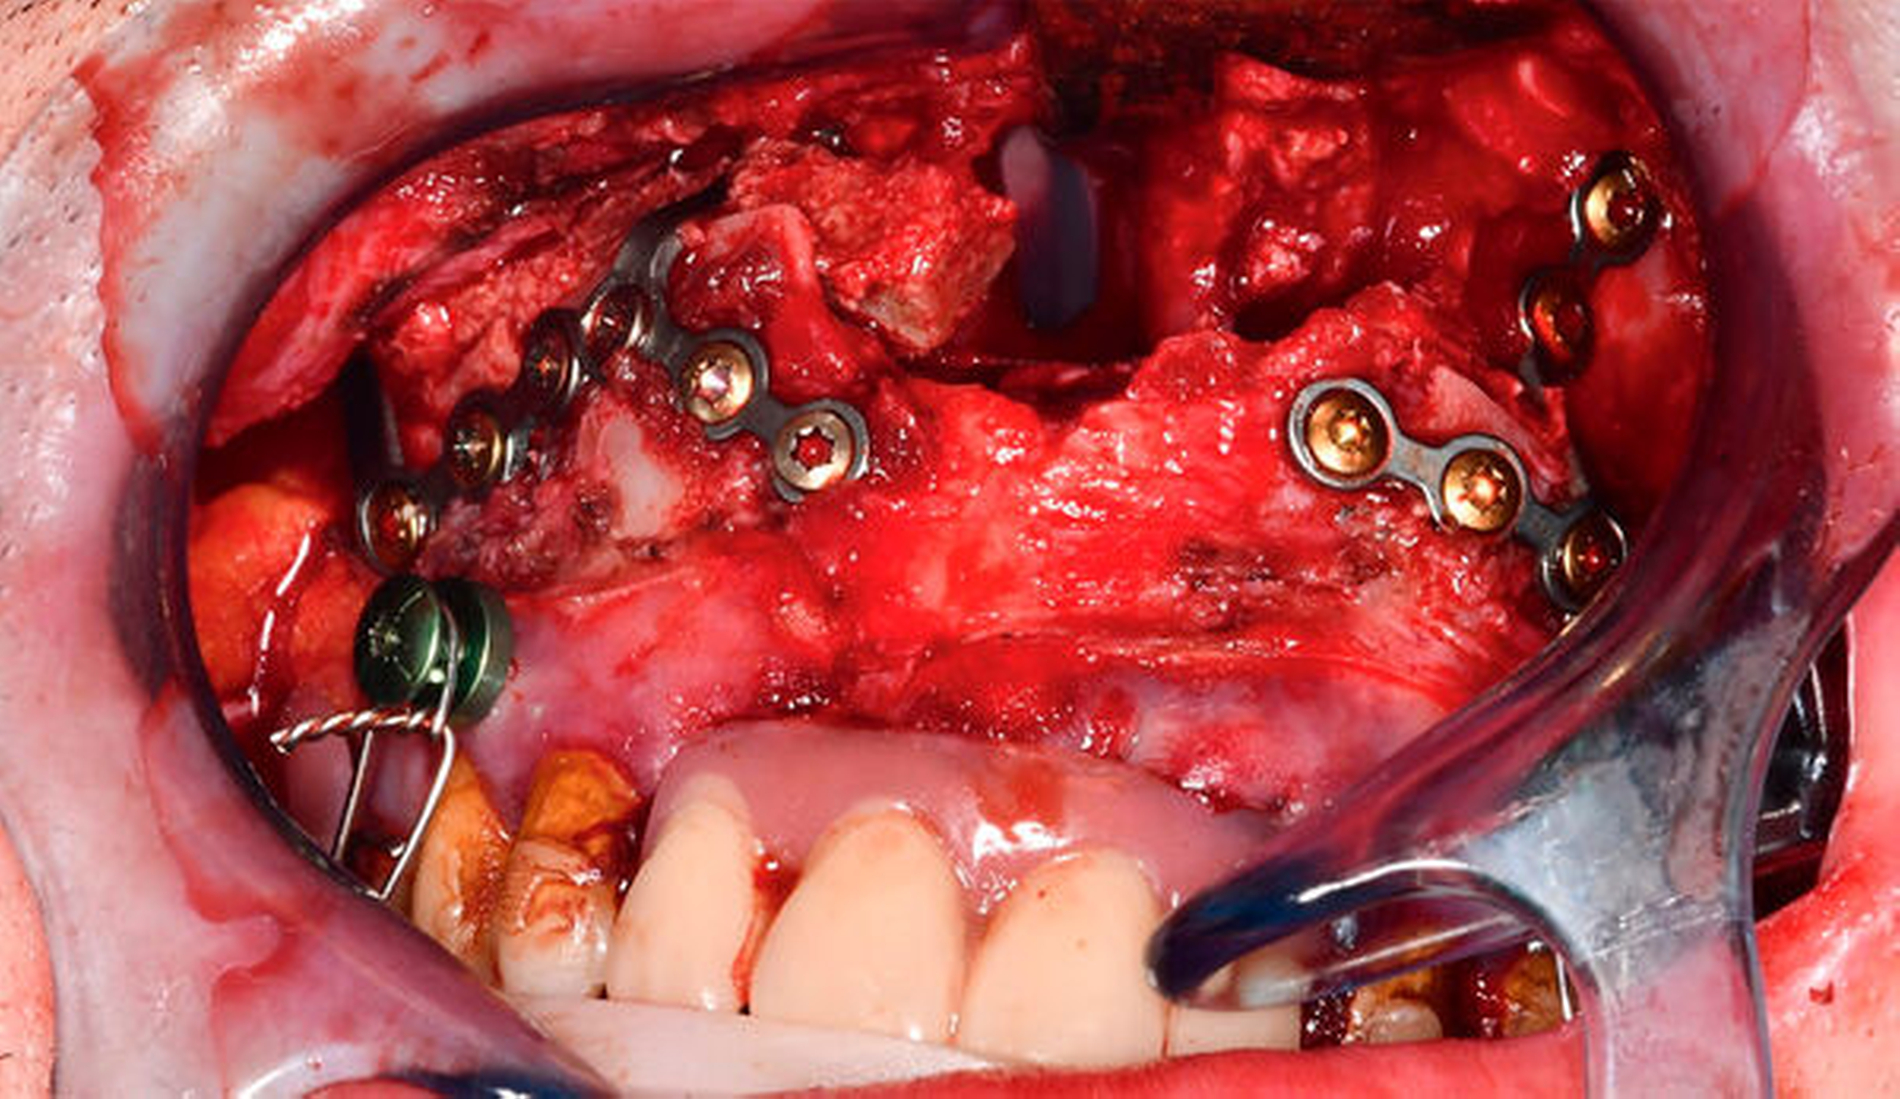

Nach Extraktion der nicht erhaltungswürdigen Zähne 17, 16, 12–27, 36, 46 und 47 und Eingliederung der präformierten Ober- und Unterkiefer-Intermediatprothese folgte die Oberkieferosteotomie in der Le-Fort-I-Ebene mit Neuausrichtung und Osteosynthese unter Verwendung eines CAD/CAM-gefertigten Okklusions-Zwischensplints. Ein zeitgleich gehobener und als Interpositionsosteoplastik eingebrachter kortikospongiöser Knochenspan vom Beckenkamm diente zur Vergrößerung der knöchernen Anlagerungsfläche nach Oberkiefervorverlagerung (Abbildung 4). Die anschließende Darstellung des rechten Kiefergelenks erfolgte über die Extension des präaurikulären Zugangs entlang der vorbestehenden Narbe nach retromandibulär, die Darstellung des linken Kiefergelenks über einen nach parietal extendierten präaurikulären und zusätzlich retromandibulären Zugang.